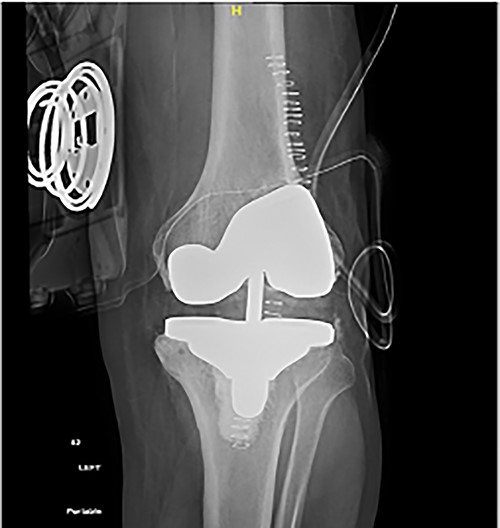

Long weight-bearing knee radiographs showed severe osteoarthritic changes, 18° knee genuvarum and extension deformity of the left distal femur (Fig. 2). Skyline view showed severe arthritic changes (Fig. 3).

Preoperative plain radiographs; (A) severe osteoarthritic changes affecting the left knee with narrowing of the medial knee joint compartment; (B) left femur with dorsal angulation above the condyles and severe patella baja.